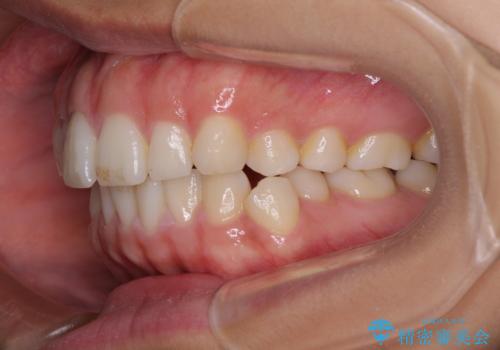

【モニター】突出した前歯 補助装置を併用したインビザライン矯正

- 上下前歯が非接触となり、前方に突出していることを気にして来院された患者様です。

咬合力が強く、全体的に歯がすり減っているため、インビザライン単独での上顎歯列移動は困難と判断し、補助装置により上顎歯列を後方移動させ、その後インビザラインにて仕上げていくこととしました。

補助装置なしでも改善できる可能性はありましたが、補助装置で確実性を上げ、短期間できっちりと仕上げることができました。